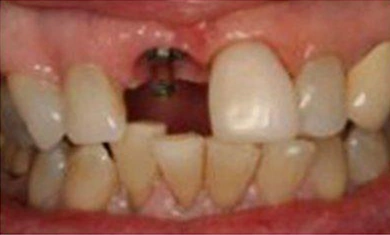

Our Gallery of Happy Smiles

Since 1983, 80 Park Avenue Dental has been creating and improving smiles in New York. You can see just a few of those smiles here in our smile gallery. If you would like to make an appointment with our dentists, Dr. Barry Sporer and Dr. Bradley J Cutler, and add your own smile to our gallery, please call 212-697-5988 today.